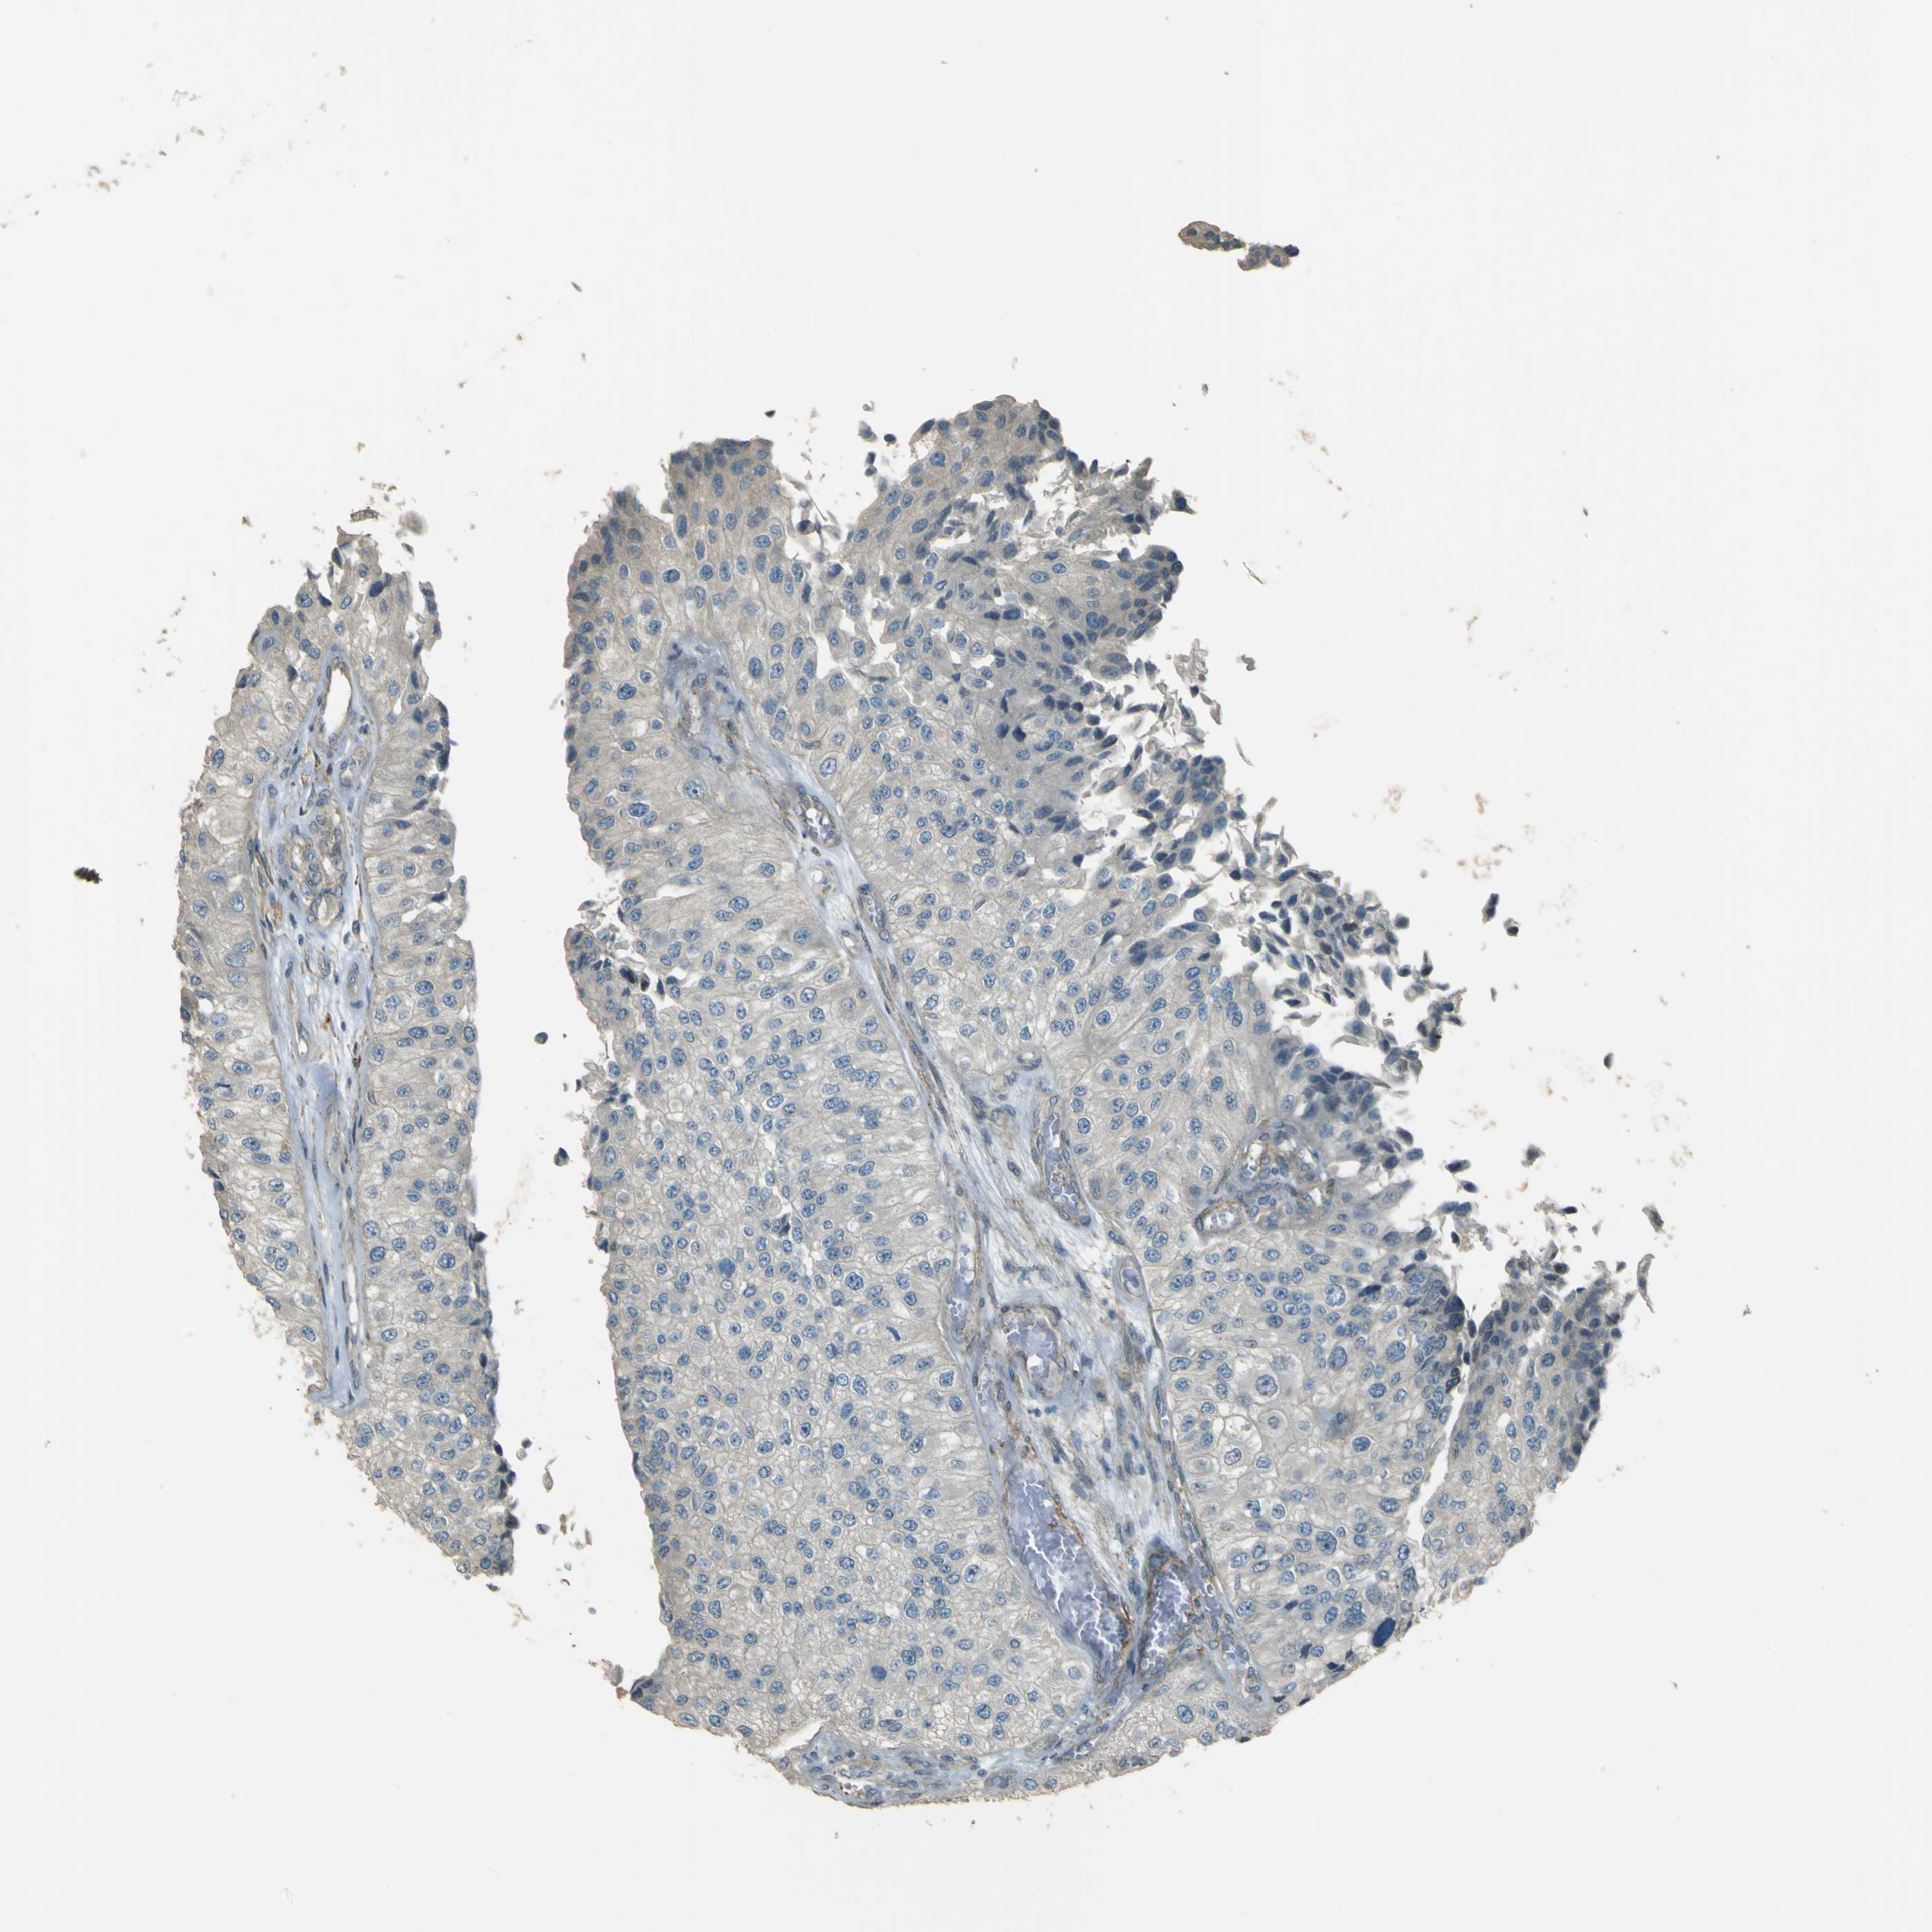

UROTHELIAL CANCER - Protein expressioni

A mouse-over function shows sample information and annotation data. Click on an image to view it in a full screen mode. Samples can be filtered based on level of antibody staining by selecting one or several of the following categories: high, medium, low and not detected. The assay and annotation is described here.

Note that samples used for immunohistochemistry by the Human Protein Atlas do not correspond to samples in the TCGA dataset.

Antibody stainingi

Antibody staining in the annotated cell types in the current human tissue is reported as not detected, low, medium, or high, based on conventional immunohistochemistry profiling in selected tissues. This score is based on the combination of the staining intensity and fraction of stained cells.

Each image is clickable and will lead to virtual microscopy that enables deeper exploration of all samples and also displays staining intensity scores, fraction scores and subcellular localization as well as patient and tissue information for each sample.

Antibody HPA011185

Urothelial carcinoma, Low grade

Urothelial carcinoma, High grade